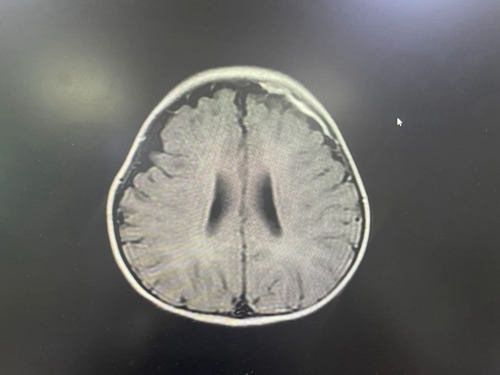

神經(jīng)內(nèi)科接診專家發(fā)現(xiàn)童童臉色蠟黃、手腳冰涼、意識模糊、嗜睡、前囟飽滿,檢測結(jié)果顯示患兒血感染指標是正常高限值的30多倍,經(jīng)過核酸檢測排除新冠病毒感染后,專家判斷可能是中樞神經(jīng)系統(tǒng)感染。結(jié)合腰椎穿刺術(shù)、腦脊液化驗、頭顱磁共振、腦電圖等一系列檢查,最終童童被確診為化膿性腦膜炎合并膿毒性休克。情況危急,必須立即救治,如果拖延,可能會遺留其他神經(jīng)系統(tǒng)后遺癥:致殘甚至危及生命。